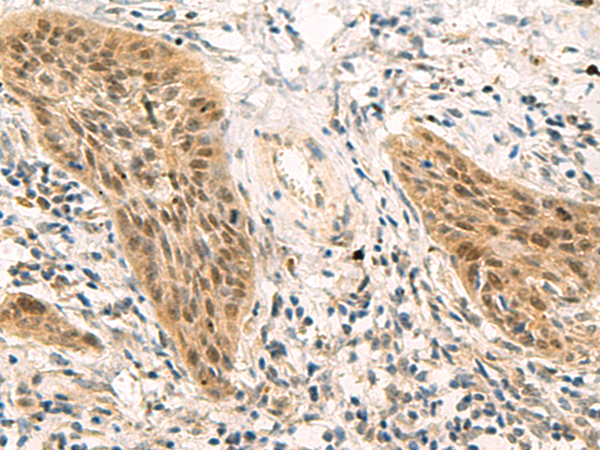

IHC positive control:

Human esophagus cancer

IHC Recommend dilution:

50-200